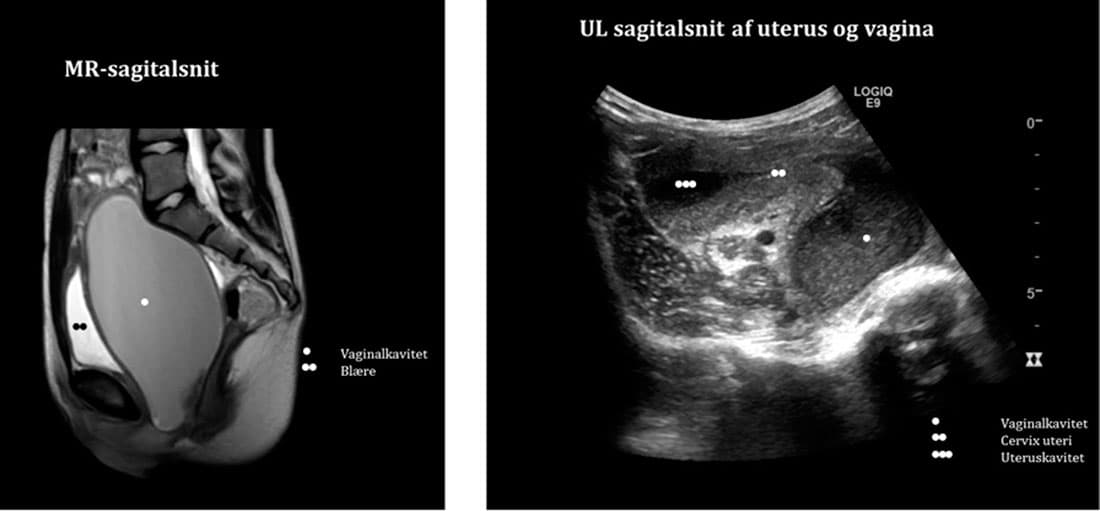

En ultralydskanning af nyrer og urinveje viste en stor, velafgrænset kavitet retrovesikalt med homogent indhold. Kaviteten havde forbindelse til uterus opadtil. Radiologisk havde man mistanke om en lukket jomfruhinde, hymen imperforatus (HI). Ved en gynækologisk vurdering kunne diagnosen ikke fastslås. En efterfølgende MR-skanning viste en svært dilateret vaginalkavitet. Indholdet var hyperintenst på T1-vægtet sekvens med yderligere hyperintensitet på gradient T1-fat saturation-sekvens, hvilket var foreneligt med hæmatokolpos.